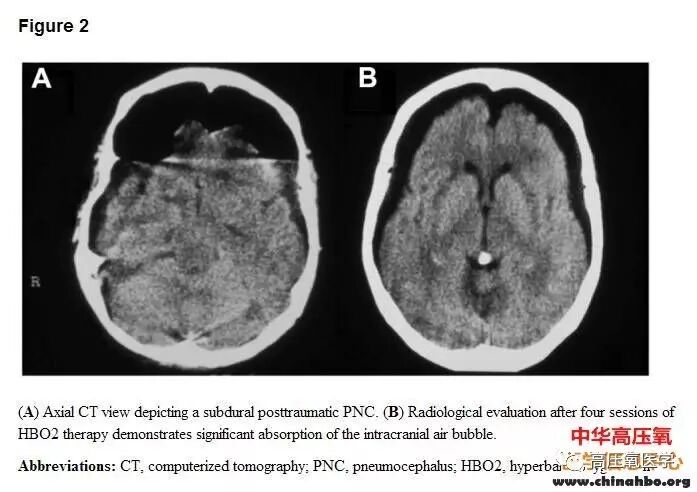

图片

气泡在硬脑膜下,高压氧治疗4次后。